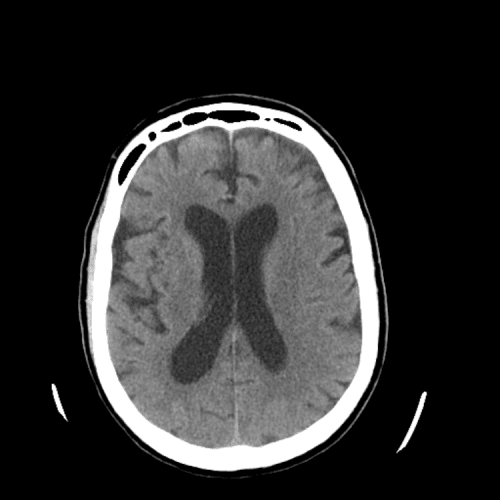

Case #3